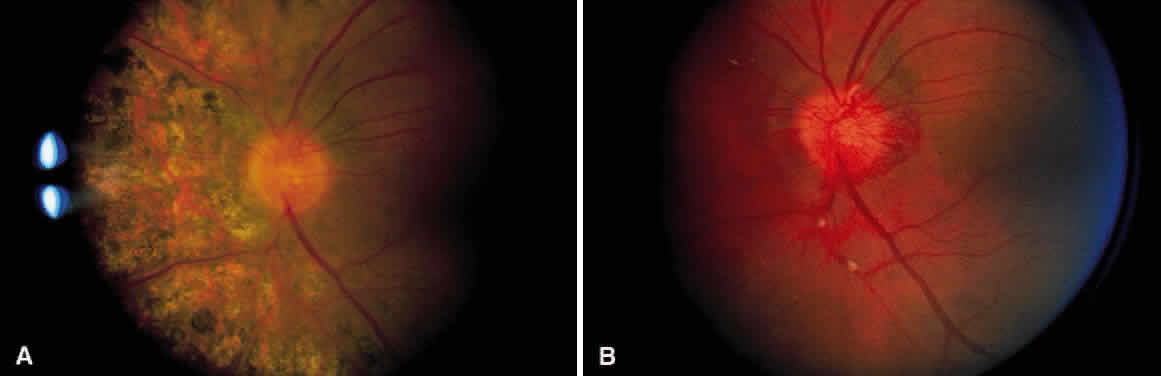

Henry Eales offered his patients a mixture of laxative, digitalis, and belladonna. Other remedies have included vitamin C, thyroid extract, and high-dose steroids. Because of the previously reported association with tuberculosis (TB), empirical anti-TB therapy is used in India.5 None of these treatments have been conclusively beneficial. Laser photocoagulation is the treatment of choice for the neovascularization of Eales' disease.1112 Numerous investigators have demonstrated regression of neovascularization with light-intensity scatter photocoagulation applied to the nonperfused peripheral retina and to the junction of perfusion and nonperfusion (Fig. 7). Vitrectomy can be used for removing persistent vitreal hemorrhages and fibrosis, often with good results.13 No treatment is known to prevent or reverse the nonperfusion or capillary dropout.

Fig. 7. A. Neovascularization of the disc. Notice the segmental exudative arteriolar sheathing. B. Same patient as in Figure 7A, 2½ years later. The patient had regression of the neovascularization after treatment with scatter photocoagulation of nonperfused retina. Areas of arteriolar sheathing previously observed are no longer present.